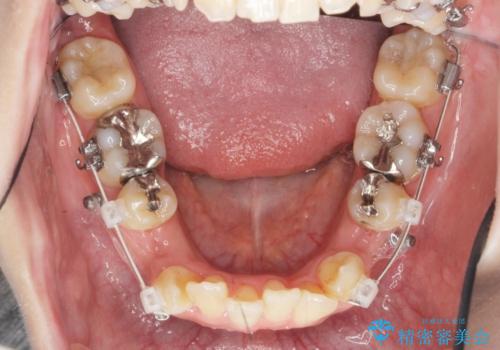

八重歯を矯正治療で治したい!

- 八重歯・がたつきのある歯並びの改善を求めて来院されました。

全部の歯が入り切るスペースがなかったため、小臼歯4本を抜去しワイヤーを用いたマルチブラケット矯正を選択しました。

歯並びの改善と共に、歯ブラシがしやすくなった!と喜んでいただくことができました。